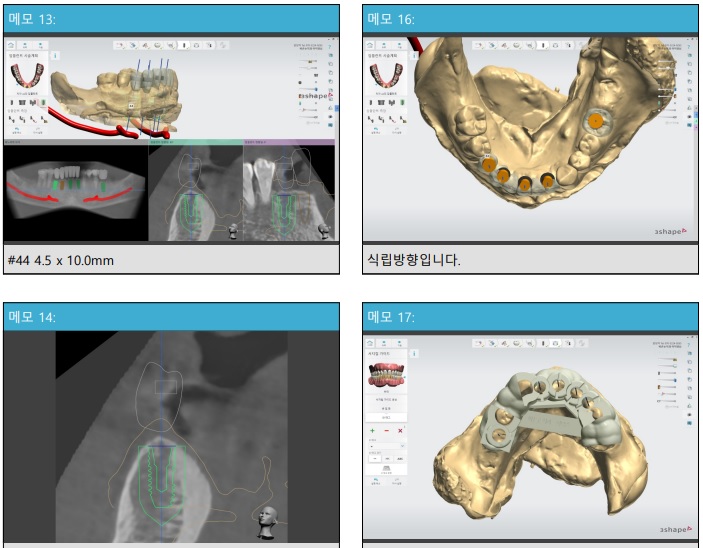

위 그림과 같이 3D-CT 사진을 통해

임플란트의 식립위치, 방향, 각도 등을 분석하여

네비게이션 임플란트 가이드를 제작합니다

치아들 사이에 껴있는 플라스틱이 <네비게이션 임플란트 가이드> 입니다.